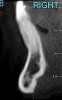

Fig 18. CBCT sagittal view shows no bone on the labial aspect and 2.5 mm bone thickness on the lingual aspect.

Figure 18